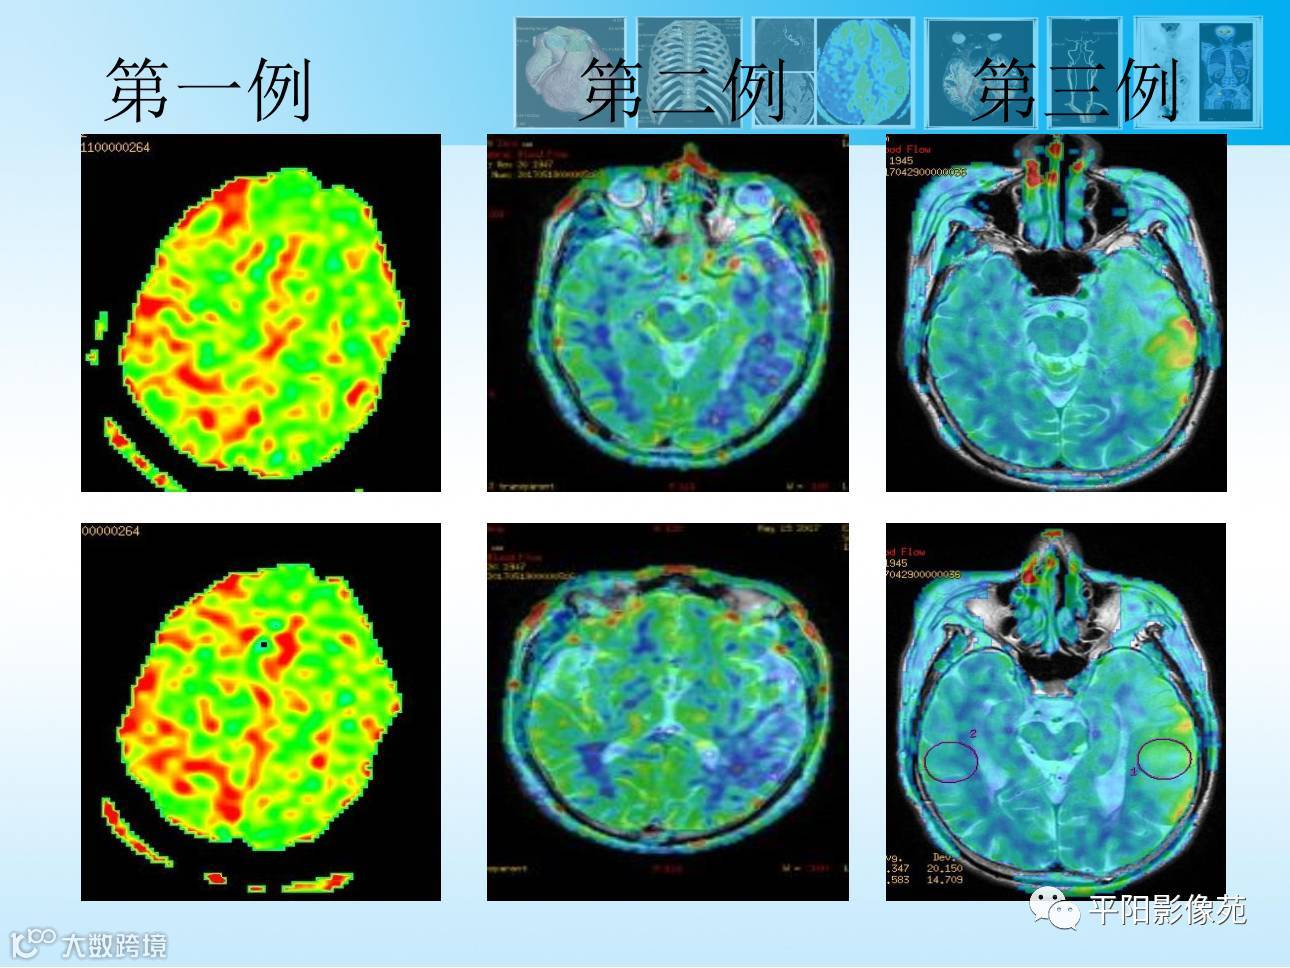

【MR功能成像专题2】3D-ASL灌注成像篇

导读:动脉自旋标记ASL成像,是一种完全无创的、不需注射造影剂的灌注成像方法,临床应用广泛。